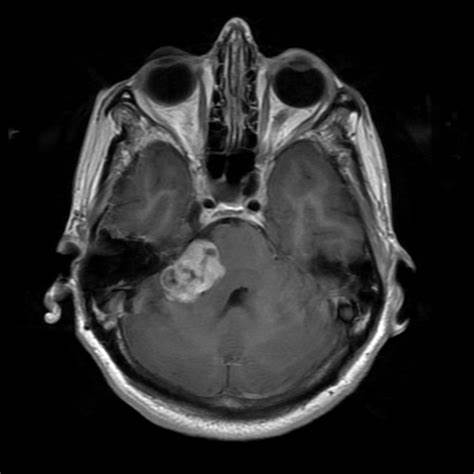

自18世纪一次发现听神经瘤以来,显微外科手术已取得进展。从那时起,在麻醉、显微镜的结合、医疗器械和神经监测系统的发展等方面都取得了进步,以帮助肿瘤切除和优化病人的治疗结果。听神经瘤相对少见,估计发病率为每年每10万人1.1例,生长速度变化不大,但一般生长缓慢。由于听神经瘤通常不会危及生命,临床医生需要考虑患者的长期后果,不仅要考虑手术结果,还要考虑影响生活质量(QoL)的结果。显微外科手术是的治疗方法之一,还包括观察和立体定向放射治疗。

传统上,较大的肿瘤伴随面神经的附着或伸展,通常采用近全切除的方法来处理,以优化脑神经功能,降低治疗后的发病率。较近的一项研究发现,近全切除组患者的心理健康评分明显低于行全切除的患者,这可能是由于残余肿瘤的持续存在造成了潜在的心理健康损害。为此,手术全切和提高生活质量如何平衡成为神经外科医生的较大挑战。

听神经瘤手术如果切除了面神经,手术后会让患者面瘫。美国犹他大学医院神经外科教授William T. Couldwell教授表示,可以使用电生理监测来提高对面神经的保存率。在手术过程中不断监测面神经的状态,以降低手术切除听神经瘤的并发症发生率。电生理监测向外科医生提供反馈,允许神经识别、描绘其过程,以及通过在损伤发生之前发出神经活动干扰信号来保护神经干。美国犹他大学医院拥有着国际治疗听神经瘤的各种前沿仪器、技术,William T. Couldwell教授能熟练应用各种现代化高科技手术设备,而这些前沿设备也确实起到了大的作用,在William T. Couldwell教授的听神经瘤显微手术下,其面神经基本都得到了保存。

传统上,保留手术后的听力比面神经表现更有挑战性。造成这种差异的确切原因尚不清楚。也就是说,听神经瘤的手术切除治疗面神经和听神经是温和的。同样的外科治疗,而面神经保留率在90%以上,乙状窦后入路后听力保留在30%-50%之间。法国巴黎Lariboisiere大学医院神经外科教授兼主席、经内镜及颅底手术的国际高手Sebastien Froelich教授也支持了以上的结论。在Sebastien Froelich教授显微外科手术下,只要是3cm以下的听神经瘤,教授的手术基本均为这些患者保留了面神经。而听力保留率就相对低一些,只有患者术前听力没有损伤,Sebastien Froelich教授都能为其保留听力,而对于听力损伤的听神经瘤患者想保留听力,教授虽然也能做到,却表示难度确实大的多。